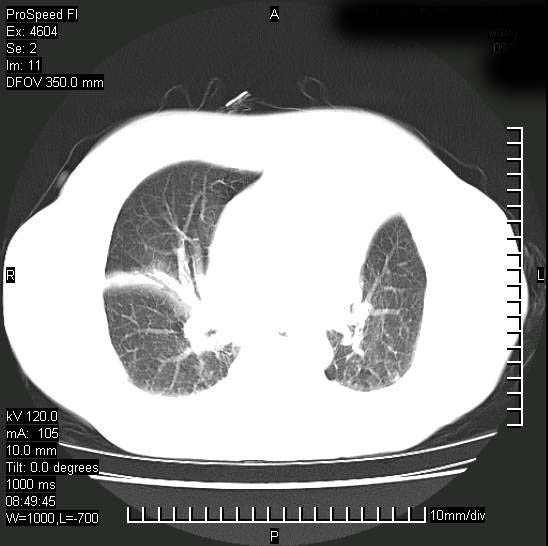

标题: CT15528:女性,79岁,近几日晚上高热,39度,仍咳少量血

十几年前曾患肺结核,一周前突咳血约100ml,中性粒细胞稍高,诊断两上肺陈旧结核,下肺炎症,给予抗炎治疗,近几日晚上高热,39度,仍咳少量血,4天前ct及今天ct上传。

今天ct